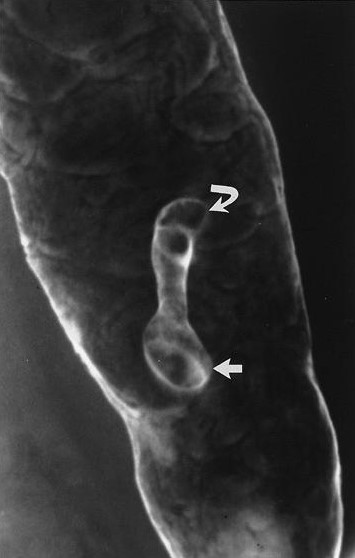

Các polyp lồi từ niêm mạc tạo hình khuyết trong vũng baryt hoặc có viền trắng do baryt phủ và khí – thấu tia x quang bao quanh khi chụp đối quang kép. Các polyp có thể có cuống (Hình 3) hoặc không. Khi nhìn chếch, các polyp có hình “mũ quả dưa”-“bowler hat”(Hình 4).

Hình 3. Polyp có cuống. Chụp cản quang kép bộc lộ một polyp có cuống dài với đầu hình củ hành (mũi tên thẳng) mọc từ niêm mạc (mũi tên cong) đại tràng xuống.